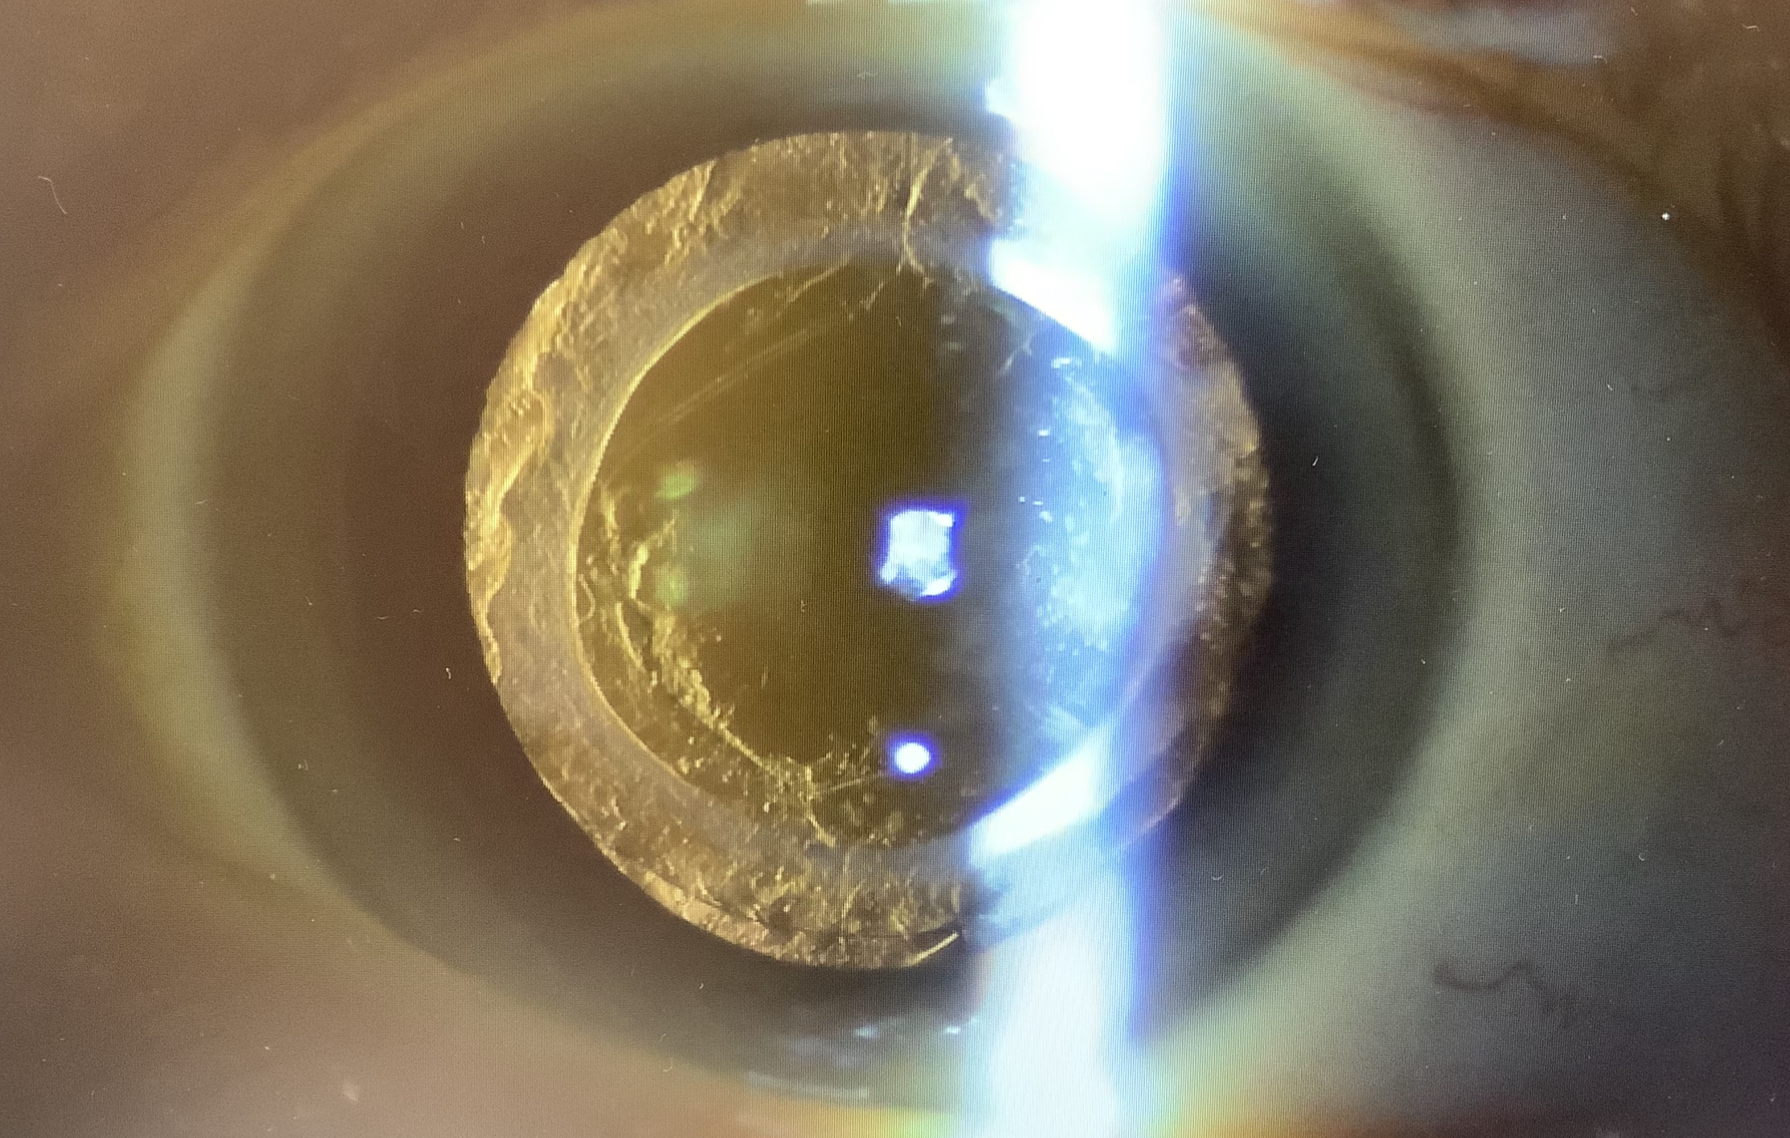

レンズは単焦点レンズできれいに眼の中に入っていますが、暗い中で光を見ると、光の線(スターバースト)がかなり強く出るようです。はっきりとした原因は特定できませんでしたが、唯一、気になったのは、後嚢の不整な濁りです。

この患者さまも後嚢は硝子体手術の時に切開されていたようですが、その切開縁に白内障の細胞が増殖して不整な濁りを作っていたので、もしかすると、これが異常光視症の原因の可能性もあるかと考え、YAGレーザーで濁りを取ってみました。